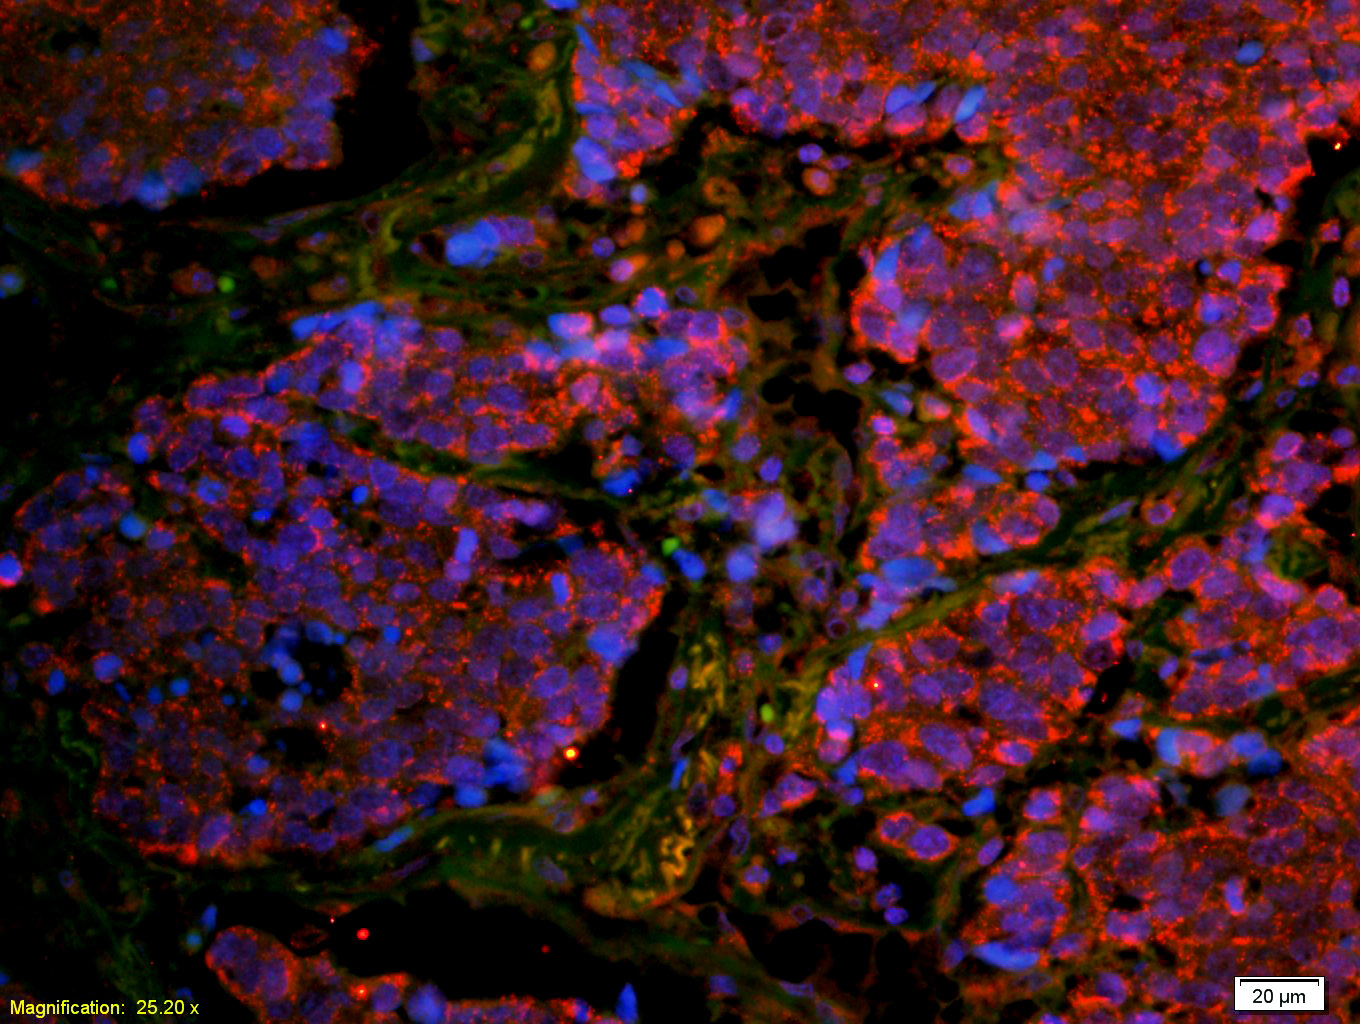

Tissue/cell: human lung carcinoma;4% Paraformaldehyde-fixed and paraffin-embedded;

Antigen retrieval: citrate buffer ( 0.01M, pH 6.0 ), Boiling bathing for 15min; Blocking buffer (normal goat serum,C-0005) at 37℃ for 20 min;

Incubation: Anti-CD8 Polyclonal Antibody, Unconjugated(bs-4914R) 1:200, overnight at 4°C; The secondary antibody was Goat Anti-Rabbit IgG, Cy3 conjugated(bs-0295G-Cy3)used at 1:200 dilution for 40 minutes at 37°C. DAPI(5ug/ml,blue,C-0033) was used to stain the cell nuclei